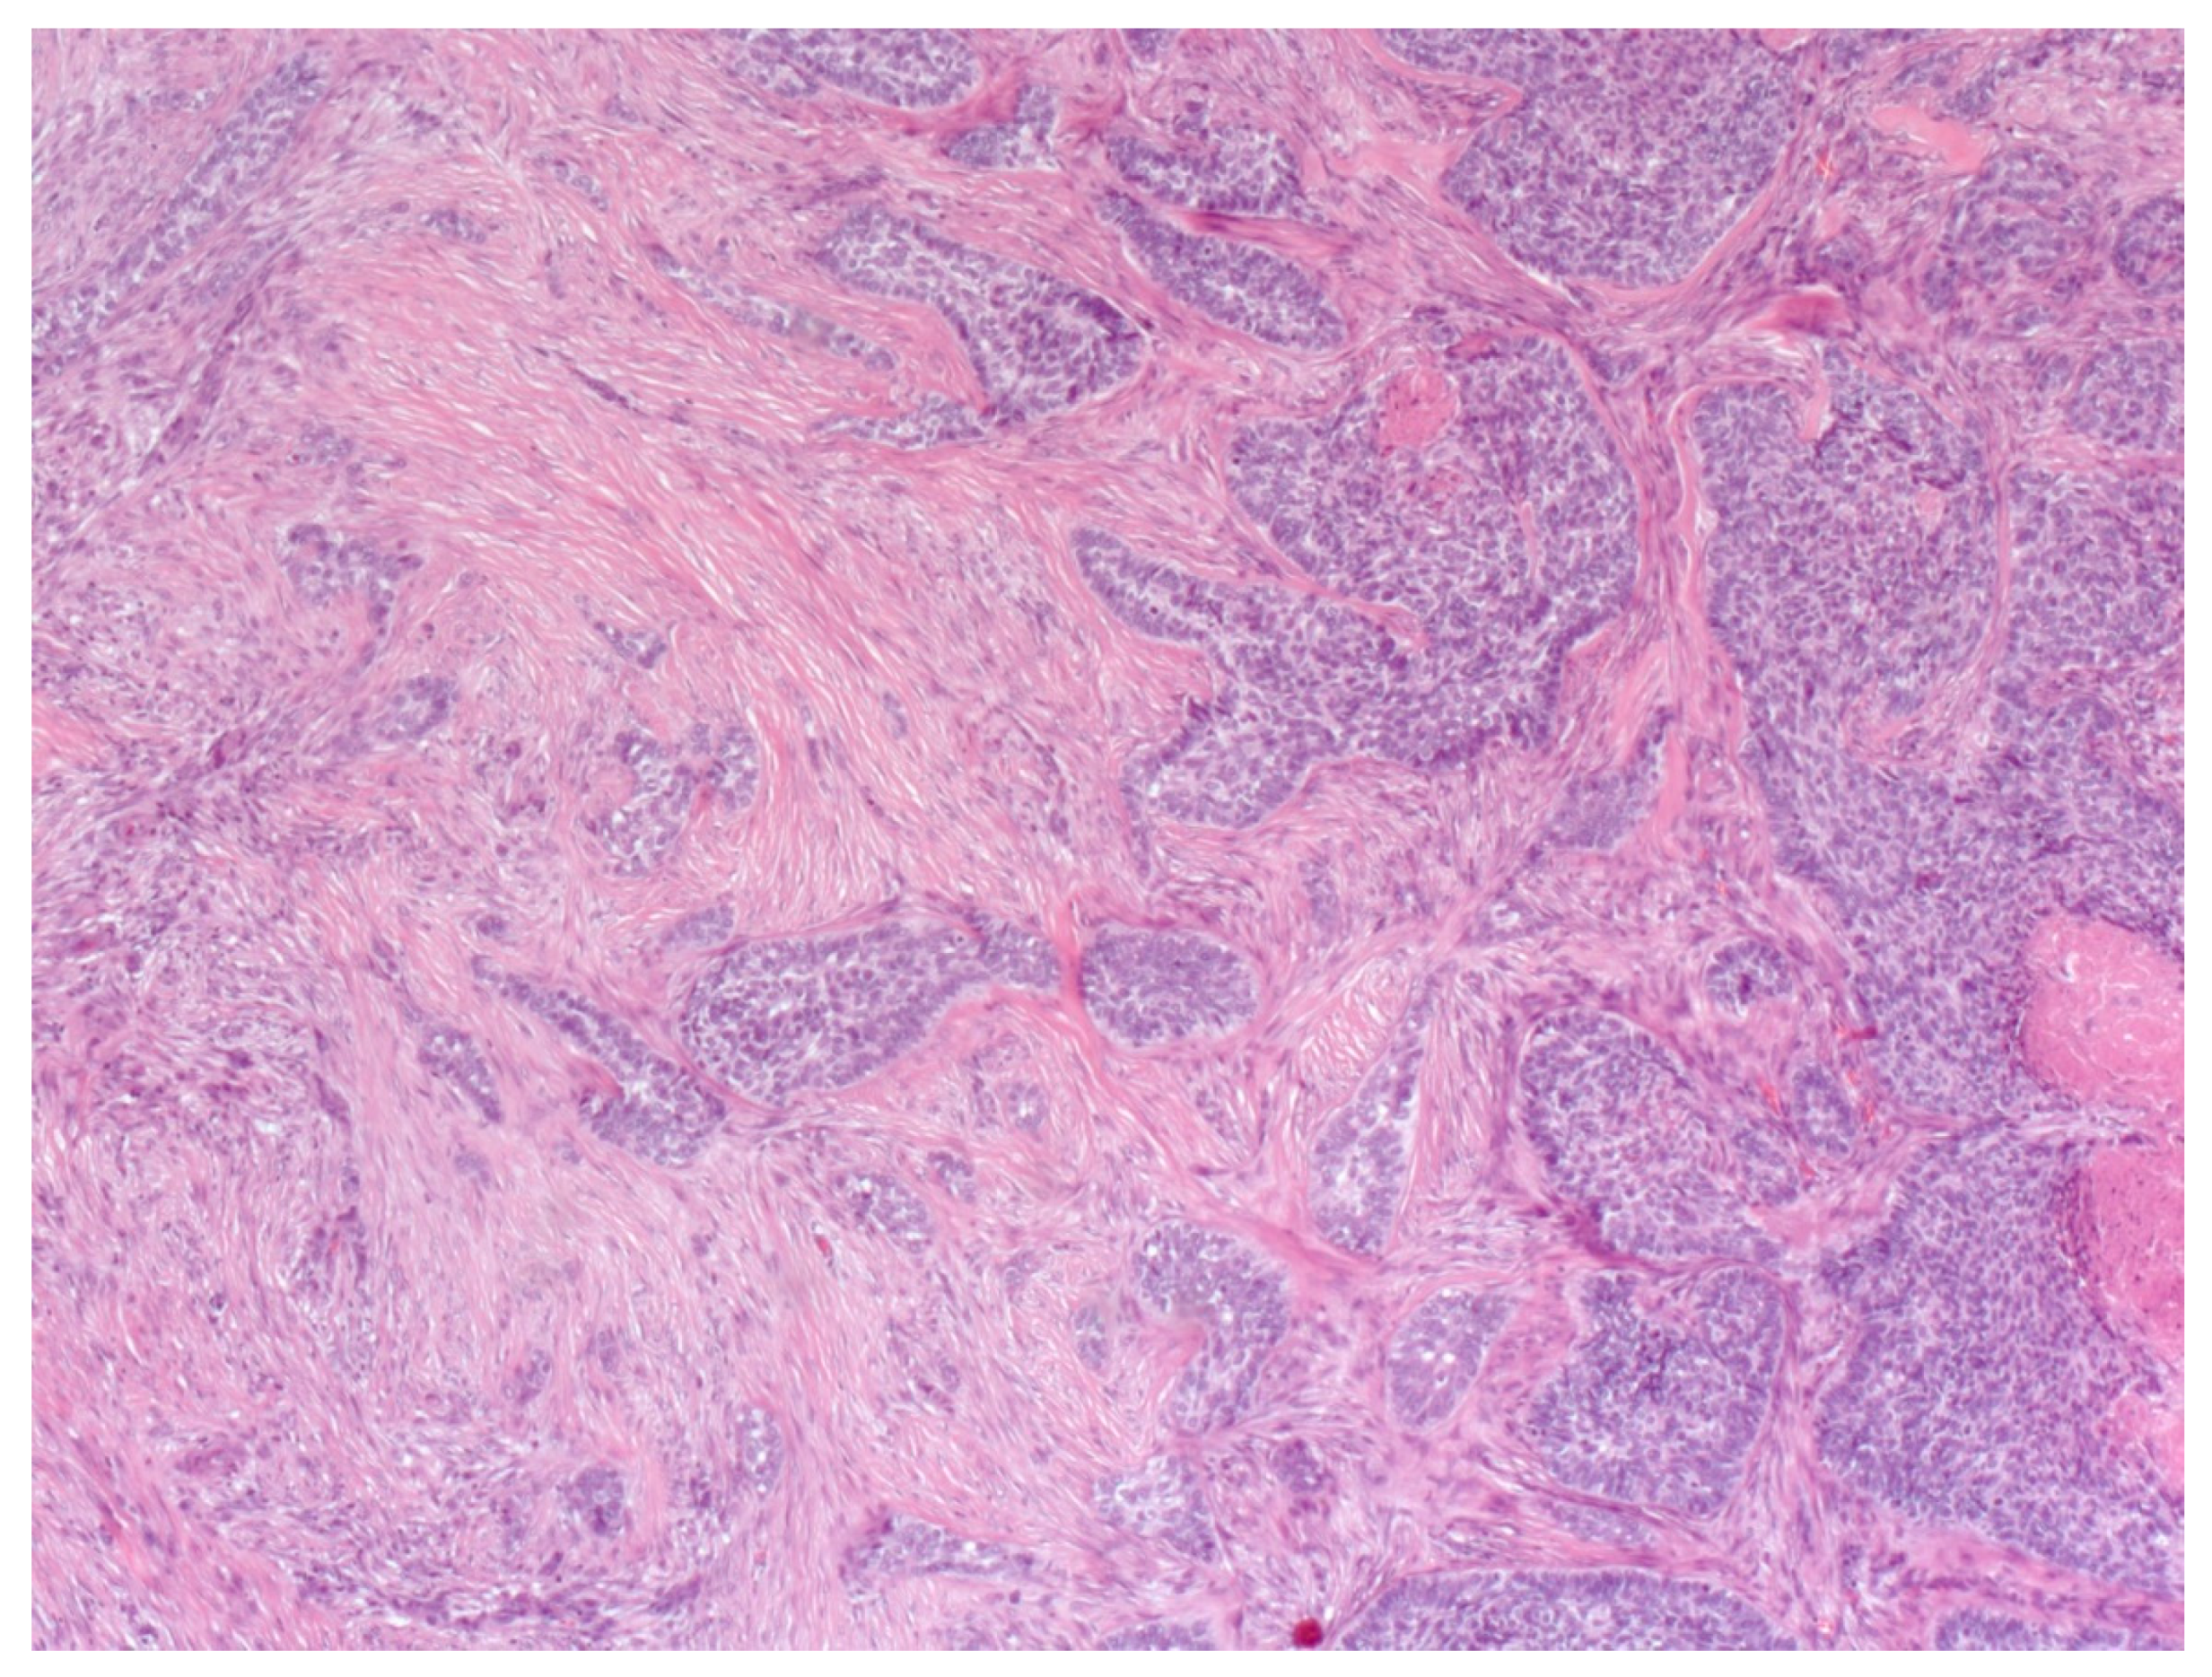

4. Histopathological Features of BCC

- Paolino, G.; Donati, M.; Didona, D.; Mercuri, S.R.; Cantisani, C. Histology of Non-Melanoma Skin Cancers: An Update. Biomedicines 2017, 5, 71. [Google Scholar] [CrossRef] [Green Version]